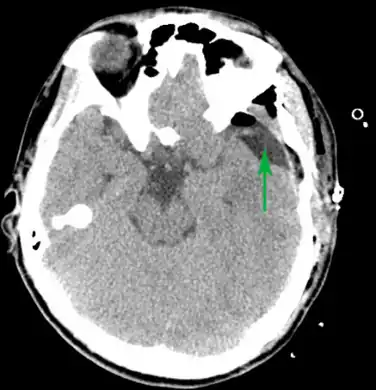

Some complications of arachnoid cysts can occur when a cyst is damaged because of minor head trauma.[19] Trauma can cause the fluid within a cyst to leak into other areas (e.g., subarachnoid space). Blood vessels on the surface of a cyst may tear and bleed into the cyst (intracystic hemorrhage), increasing its size. If a blood vessel bleeds on the outside of a cyst, a collection of blood (hematoma) may result. In the cases of intracystic hemorrhage and hematoma, the individual may have symptoms of increased pressure within the cranium and signs of compression of nearby nerve (neural) tissue.